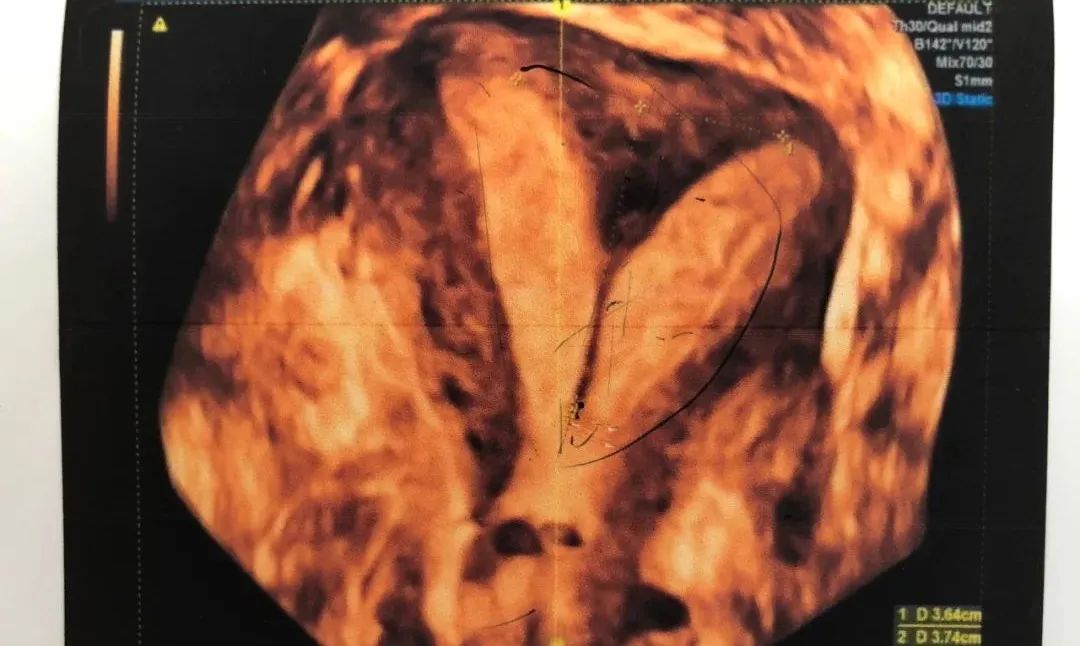

经超声检查,医生告诉王女士,她的子宫中有一道“墙”,把一个子宫腔一分为二了,医学上被称为“纵膈子宫”,一般在没怀孕的时候并没有什么症状,而怀孕后却会容易引起流产、早产等。

从王女士检查结果上看,子宫就变成了一个Y形,左右两边的宫腔都太小了。